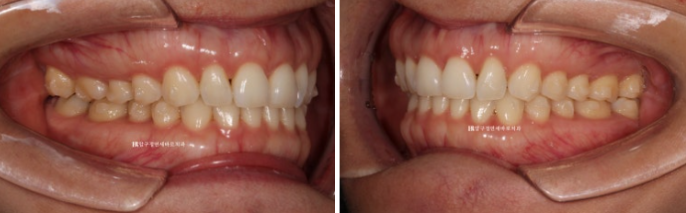

24.05

23.07~24.05

가위교합이었던 우측 상악 제 2대구치 교합도 잘 유지가 되고 있습니다.

악궁 모양과 배열이 잘 잡혔고 재제작때 미니스크류 뺀 자리는 잘 아물어서 흔적이 없습니다.

흉터가 작게 남는 경우도 있지만 흉터가 남지 않는 경우가 많습니다.